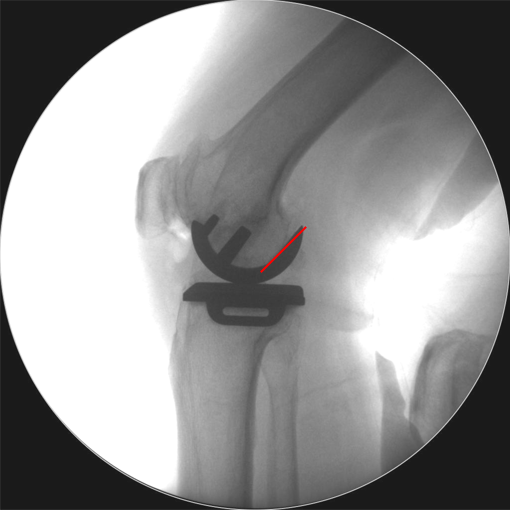

辨认bearing内的标识(透视片侧位)

bearing 内的标识:点和线段“ .—. ” 线段显示为“—”在前;点显示为“.”在后

Bearing脱位在正位片上显示股骨与胫骨假体关节面接触,侧位片显示bearing位于关节囊前方或者后方。

解读:两个点都在内侧

病例2:Bearing 破裂( X-ray侧位)

解读:股骨假体与胫骨假体间隙还存在,在图像放大4倍情况下,才依稀看到模糊的点.